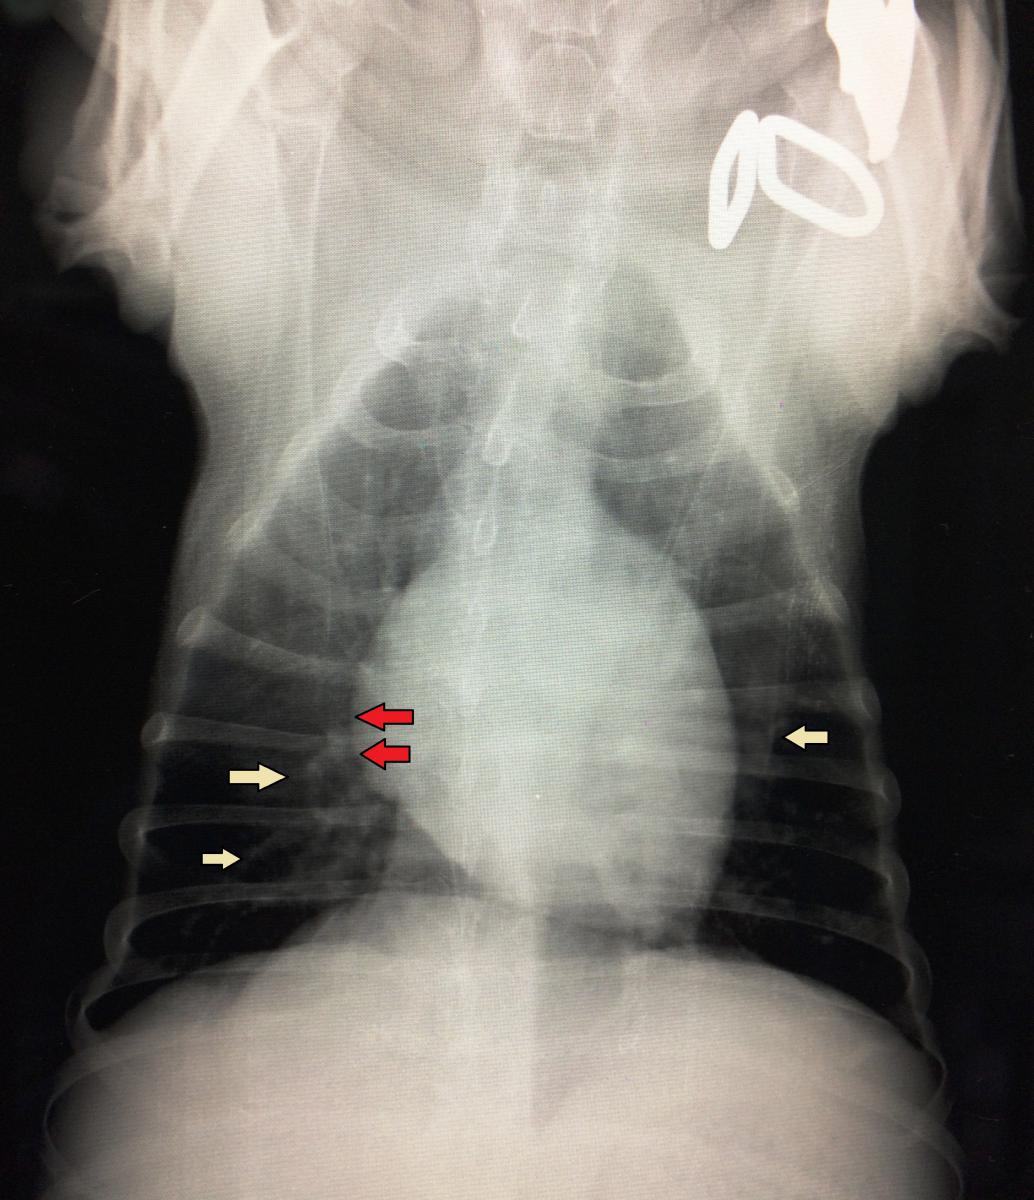

腹水 – さだひろ動物病院 松戸市新松戸の犬・猫専門動物病院。

ワンちゃんの腹部膨満 循環不全による腹水貯留– 小手指ペットクリニック。